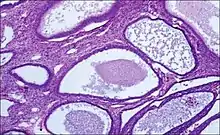

- Endometrial hyperplasia (simple or complex) - Irregularity and cystic expansion of glands (simple) or crowding and budding of glands (complex) without worrisome changes in the appearance of individual gland cells. In one study, 1.6% of patients diagnosed with these abnormalities eventually developed endometrial cancer.[6]